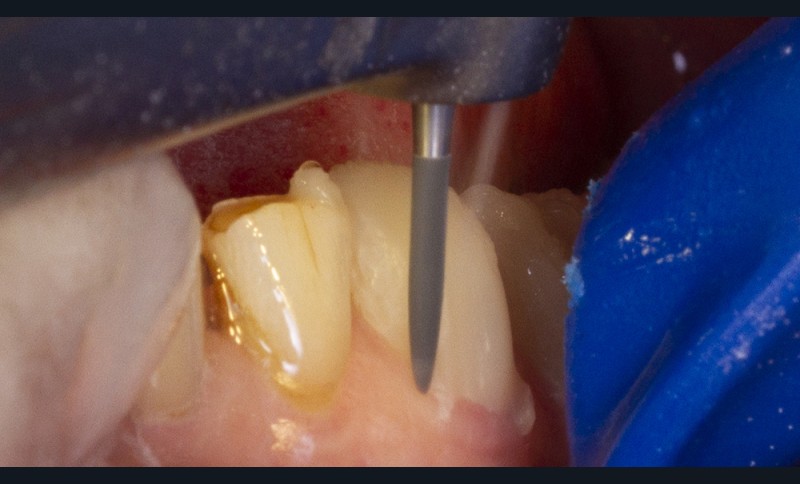

Le secteur incisivo-canin maxillaire débute la séquence thérapeutique selon la technique de pénétration contrôlée décrite par Galip Gurel [23].

Les restaurations postérieures bénéficient également de cette technique de préparation à pénétration contrôlée grâce à l’usage de fraises spécifiques. Elles s’effectuent à travers les composites collés. Ces derniers seront intégralement éliminés ainsi que toutes les anciennes restaurations sous-jacentes afin d’assurer un collage sur des tissus optimaux.